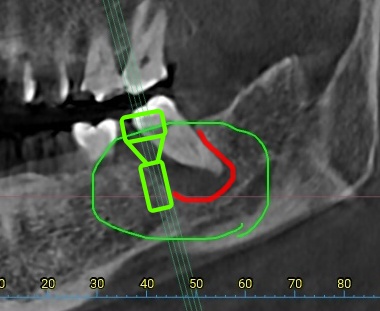

사진 1) 염증이 심한 치아를 발치하고 임플란트를 심어야 하는 상황이었습니다. 연두색 그림처럼 임플란트를 심어야 하는 상황이었죠.

사진 2) 발치를 한 뒤 한참을 기다려도, 염증이 심했던 자리에는 뼈가 차오르지 않습니다. 빨간색 실선만큼의 공간이 그대로 남아 있는 것이죠.